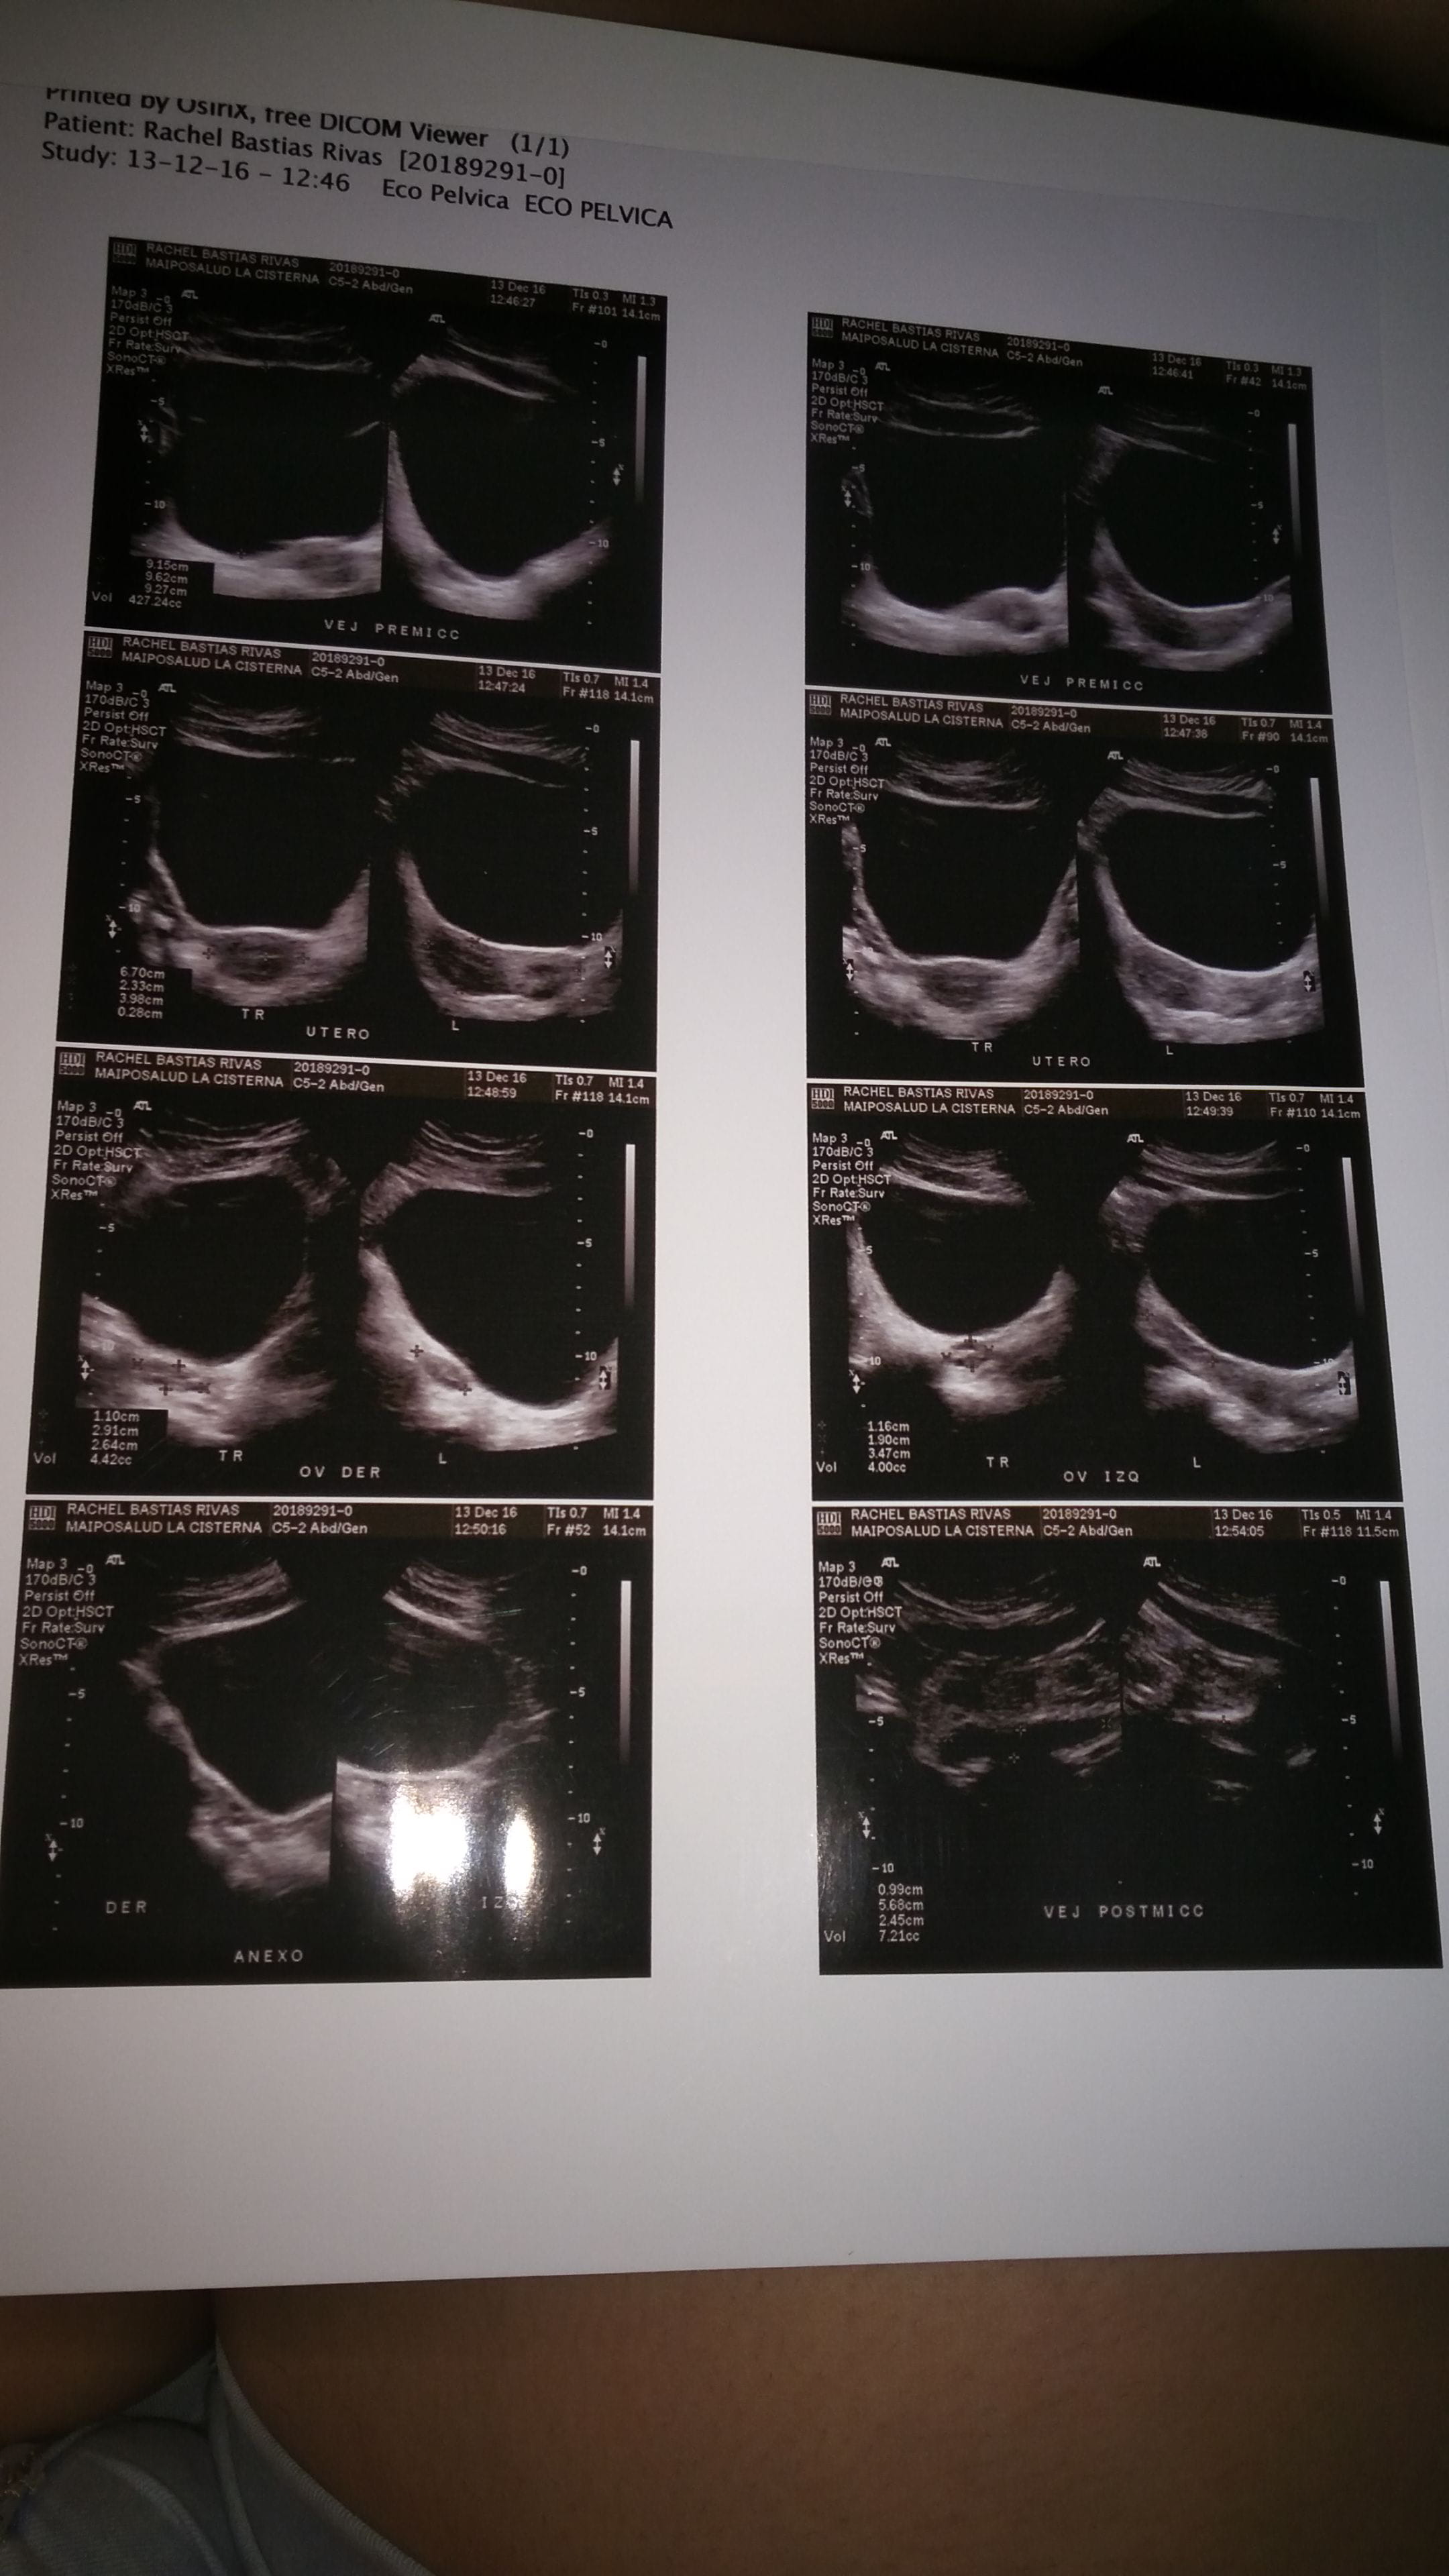

Hola, me hice una eco transabdominal y quiero saber si estoy embarazada,y me gustaria saber antes de llevarle los resultados al ginecólogo ya que tengo 17 e ire con mi mamá y no quiero que el Dr. Se lo diga a ella.Ayudenme porfavor.

Por lo que alcanzo a ver,No....y ya q vas al ginecólogo pedile que te recete pastillas anticonceptivas asi ya no tenes sustos...saludos